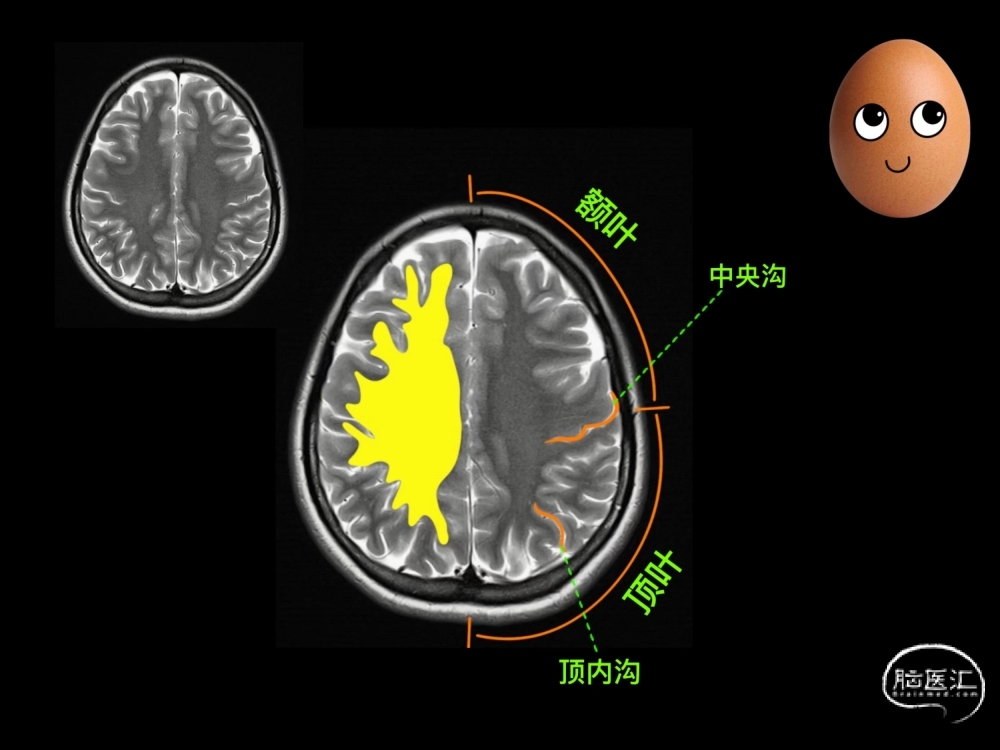

这个层面从整体上看,颇似“洋梨”的形状,故得名“洋梨样层面”。

在这个层面可以看到著名的中央沟、中央前回和中央后回,还有顶叶联络区。

中央沟

是大脑最为显著的脑沟,我们以此来分割两个主要的脑叶:前面是额叶,后面是顶叶。“Ω 征”是 指中央沟的走行,与中央前回后面凸向后方形成沟形, 酷似倒置的 Ω,是确定中央沟较为熟知和常用的征象。

中央前回

第一躯体运动区。倒“Ω”形的凸出部分是支配手的区域。而支配下肢运动的区域位于大脑半球圆顶部至半球内侧区。 该区由大脑中动脉或大脑前动脉皮质支供血。如果该部位部分受损,患者会出现手部麻痹等局限性运动障碍。

中央后回

与中央前回隔中央沟相并列。是第一躯体感觉区所在处。支配区域的分布类似于中央前回。如果该部位部分受损,患者会出现手部感觉障碍等局限 性感觉障碍。

顶叶联络区

包括顶下小叶(角回、缘上回)、顶上小叶等,负责整合并处理各种感觉。主要由大脑中动脉皮质支供血。如果该部位受损,患者会出现失用、失认、失读、失写等大脑高级功能障碍。